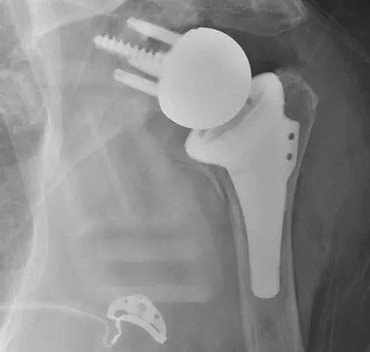

Great weeks worth of joint replacement surgeries. Anatomic , reverse, & before/after of a revision reverse. It's not work when you're having fun! Have a great weekend!